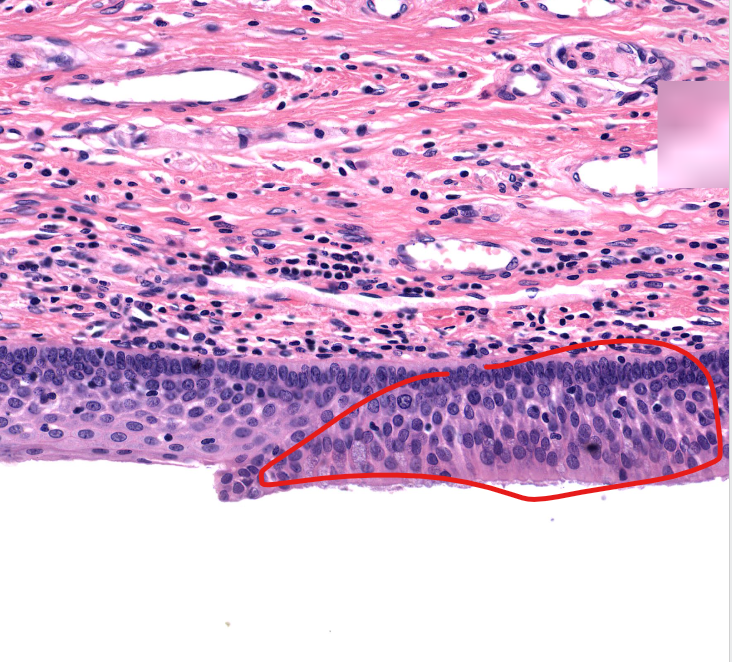

(tissue type)

respiratory epi

aka ciliated pseudostratified epithelium

found on posterior/trachea side of the epiglottis